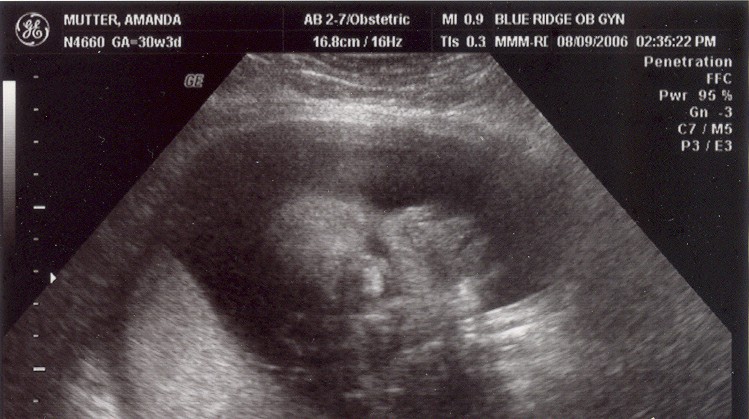

August 8, 2006: Another Ultrasound

Little did my parents know I'd be making my entrance in less than a month. The OB didn't suspect either :-)

My face is recognizable already.